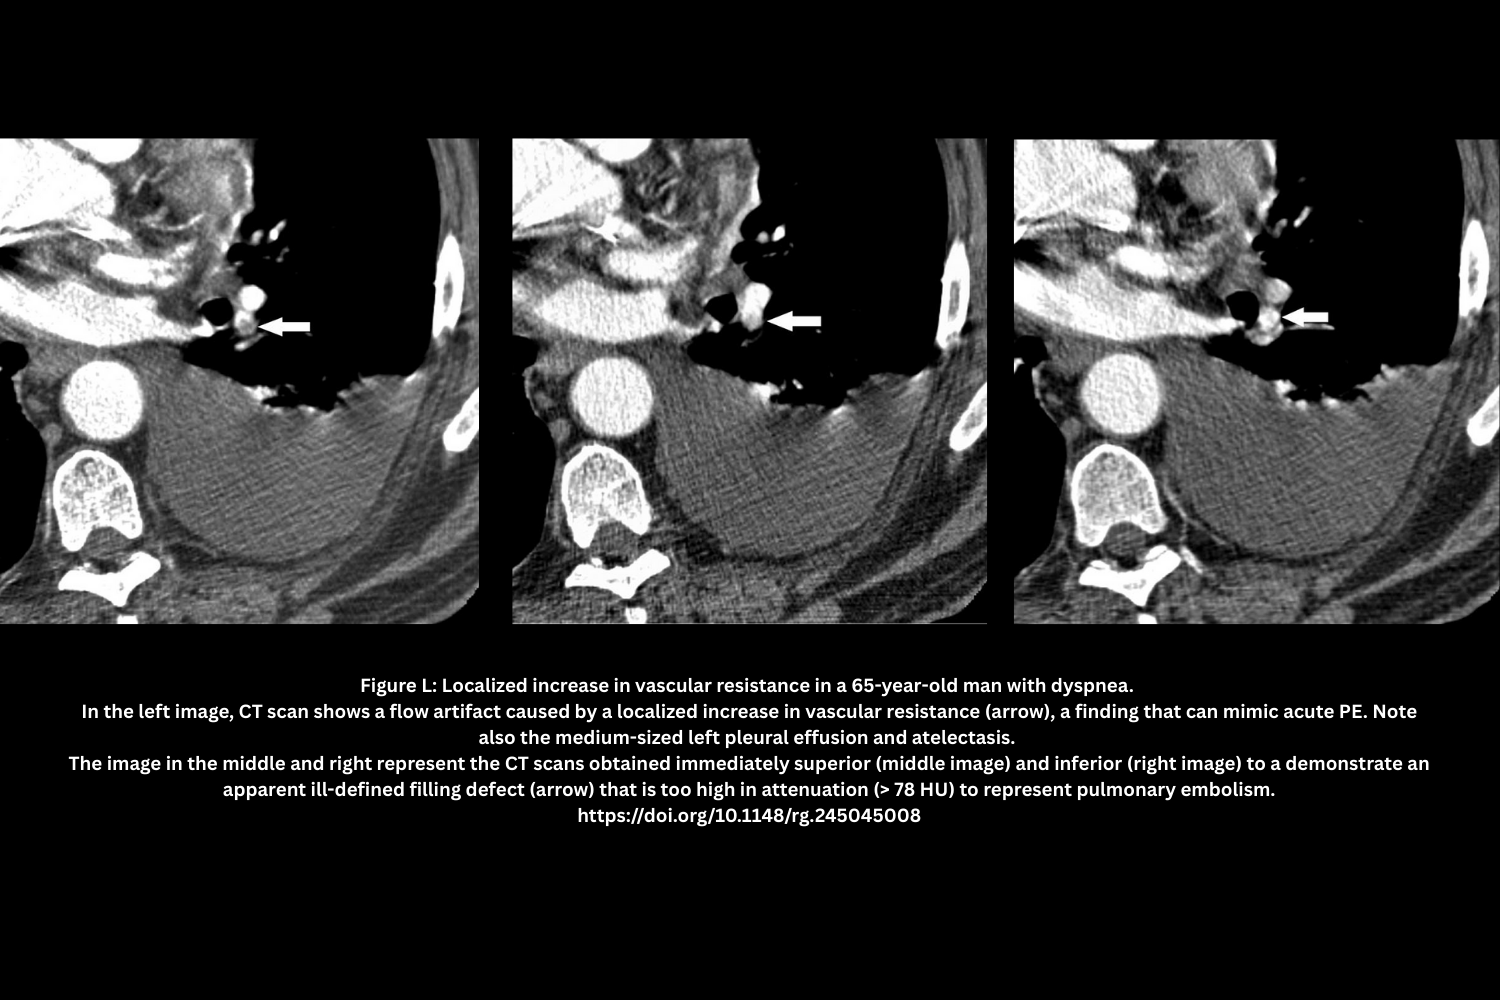

- Localized hypoxic vasoconstriction (Figure L)

- Consolidation/atelectasis → Sluggish or unopacified flow mimicking a clot.

- Attenuation often >78 HU; repeat scan with delay may clarify.